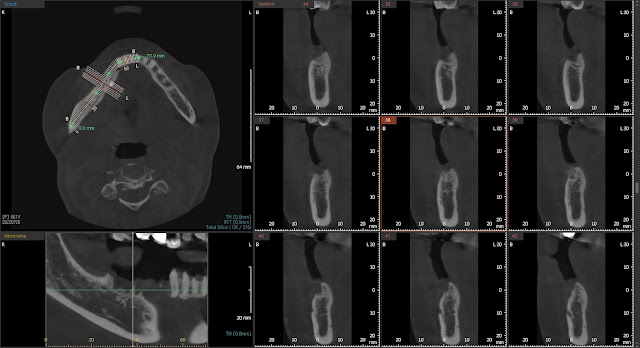

Here is a post-operative photo. Fortunately, the area of tooth #47 was placed slightly towards the lingual side, avoiding any significant risk. Additionally, the implant in the other area is not perforating through the lingual cortical bone, which is a positive outcome.

Taking into consideration the limited mouth opening of the patient, as well as the occlusion and the relationship with the inferior alveolar nerve, a mid-face X-ray was captured.

The implants had a tissue-level neck of 2.8mm and a length of 8.5mm. The implant placement was accompanied by guided bone regeneration (GBR) techniques.

However, there is a concern for potential nerve damage in the area of tooth #47, contrary to initial expectations.